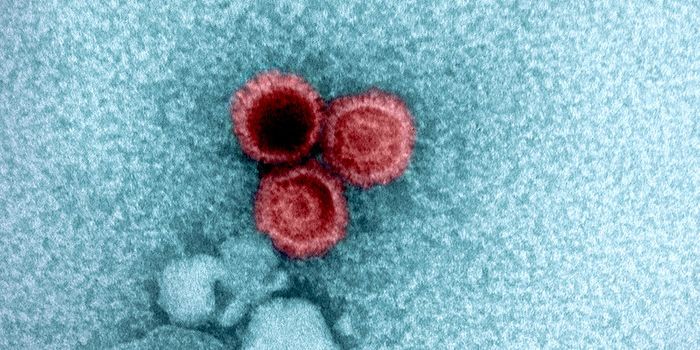

AUG 24, 2020ImmunologyOnce in the body, HIV tracks down T cells that bear the CD4 receptor. It attaches to these immune cells, fusing itself w ...